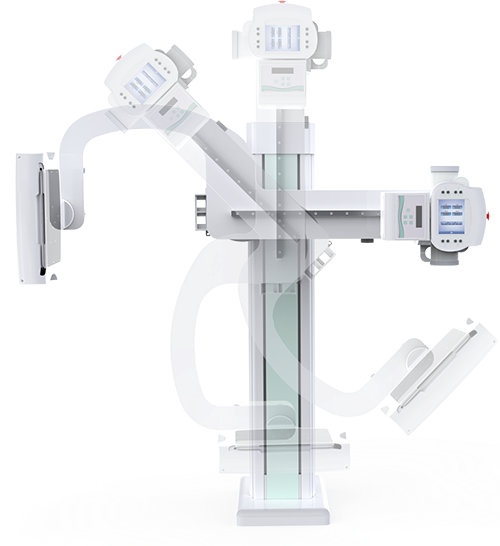

電動(dòng)旋轉(zhuǎn)內(nèi)平衡結(jié)構(gòu),可實(shí)現(xiàn)快捷擺位,滿足特殊體位的靜態(tài)與動(dòng)態(tài)檢查。

滿足不同身高的受檢者快速地進(jìn)行胸片的靜態(tài)及動(dòng)態(tài)檢查,適合大規(guī)模體檢。

SID可拉伸至1.8米,滿足標(biāo)準(zhǔn)胸片、職業(yè)性塵肺病檢查等特殊需求。